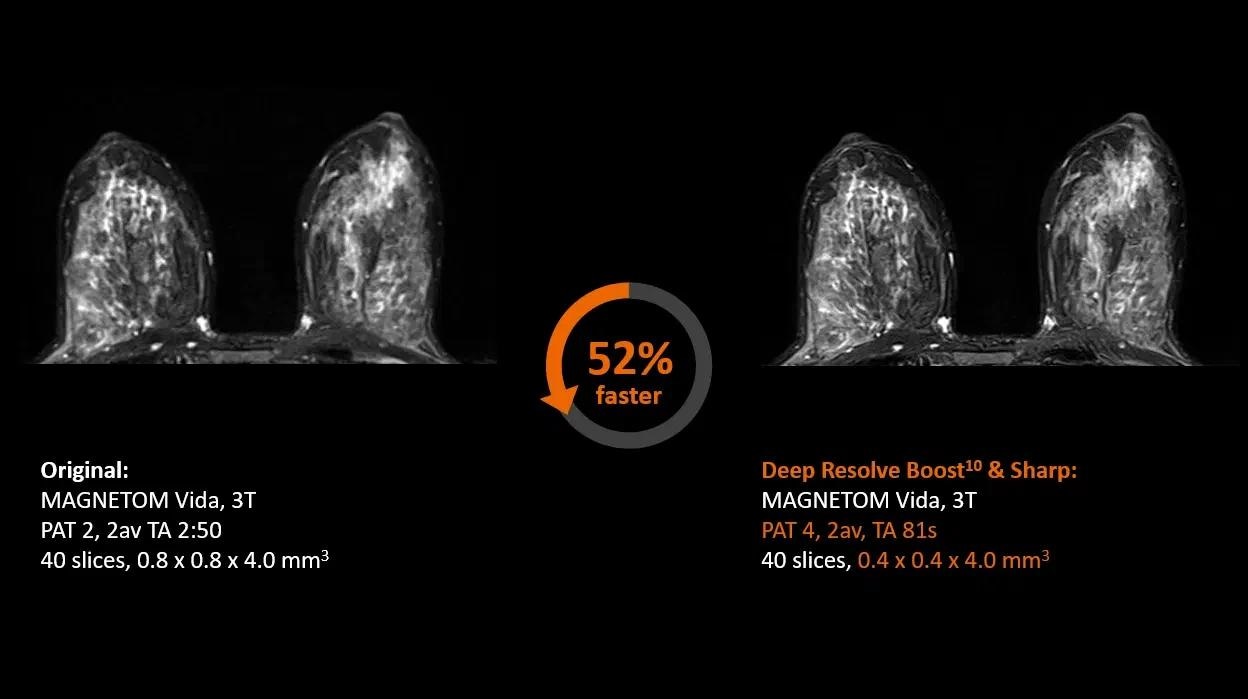

Deep Resolve5

Sharper images at a faster rate than ever before.

Deep Resolve—Faster than ever before

Deep Resolve is an AI-powered image reconstruction system that uses convolutional neural networks to expedite MR scans, making them faster than ever before. Faster scans increase workflow efficiency while boosting patient satisfaction.

Deep Resolve’s raw data-to-image reconstruction and extremely quick acquisition are game changers in MRI, allowing for the generation of actionable insights that can be diagnostically useful. In a secure digital environment, an open interface is intended to foster cooperation and co-creation. Deep Resolve technology is one step closer to creating a healthy world for all.

Body MRI

Image Credit: Siemens Healthineers